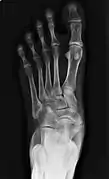

Type 2 on one foot (dark arrow) and type 3 on the other (white arrow)